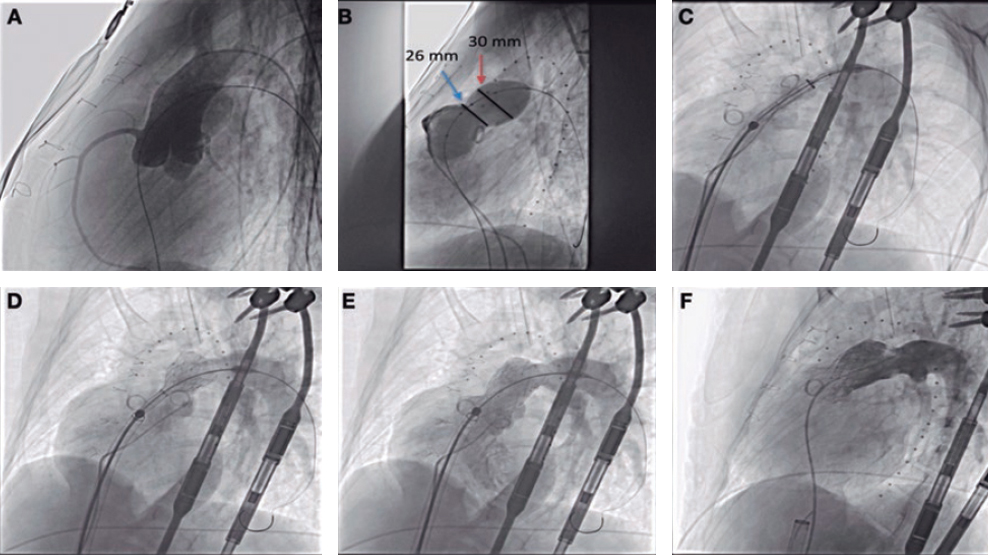

Dissection and re-entry with specific devices

Inside the hybrid algorithm36 when the CTOs show ambiguous stumps, lengths > 20 mm, and it is impossible to use the retrograde access, the dissection/re-entry technique that can be used. It is done using a specific device to achieve an easy and effective re-entry of subintimal space into the true lumen using the Stingray LP balloon with its specific guidewire (Boston Scientific, Nattick, Massachusetts, United States).

Until recently, this dissection/re-entry technique was conventionally performed using the CrossBoss and Stingray catheters. Nowadays there are times than the CrossBoss catheter is not even necessary. The 135-cm Corsair (ASAHI Intec, Nagoya, Japan) or Turnpike (Teleflex Inc, Wayne, PA, United States) catheters can be used to advance the guidewire with the microcatheter to a point where it cannot advance anymore. Once it has reached this point in the subintimal position, it is changed for the Stingray LP balloon that is inflated at 4 atm in the subintimal space. Through the 2 lateral ports situated at 180º from one another, the distal true lumen is re-entered with a rigid guidewire (Stingray wire, Hornet 14, Confianza Pro 12) using the stick and swap or multiple fenestration techniques. Then distal canalization occurs using a polymeric Pilot 200 (Abbott Santa Clara, CA, United States) or Gladius Mongo guidewire (ASAHI Intecc, Nagoya, Japan).